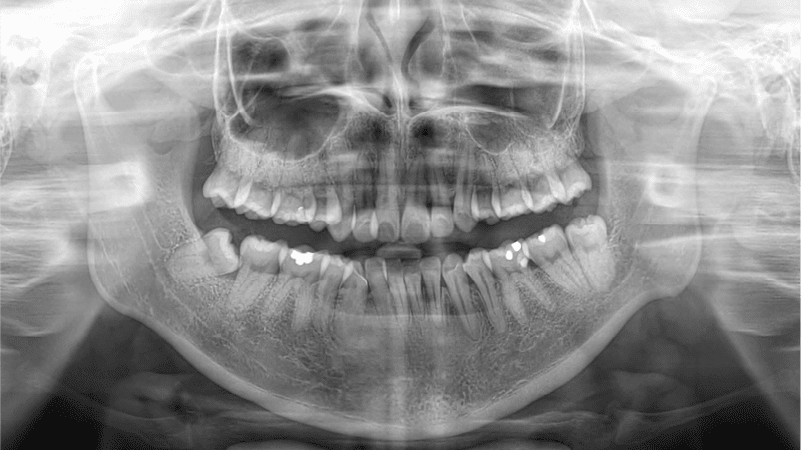

Dental xrays and 3d intraoral scanning in singapore

Why are there X-rays and 3D scans?

X-rays and 3D scans by dentists are must-haves to assess underlying dental conditions before any treatment is prescribed.

NoFrills Dental provides thorough screening of your dental health before, during and after your treatment which is highly recommended in order to alleviate any risks of irreversible damage to your teeth due to misdiagnosis.

Procedures like X-rays and thorough, in-person dental consultations with qualified dentists might seem inconvenient and costly. However, it’s essential to remember that orthodontic treatments that skip them can lead to unsuccessful treatment outcomes, root resorption, tooth motility, and even tooth loss.